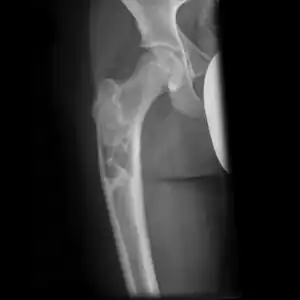

- Multloculated cavity in the long bone of the thigh, near the hip.

- Break through simple bone cyst in the long bone of the thigh, near the hip.